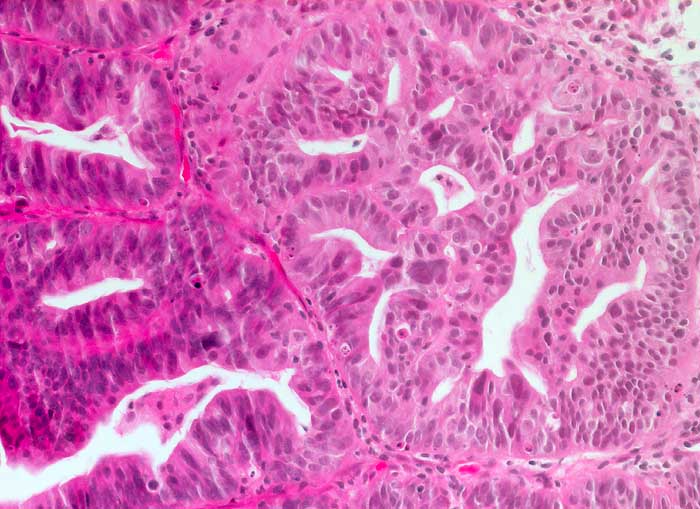

PathoPic – image database / PathoPic ID 6221 - Hoch differenziertes endometrioides Karzinom

Hoch differenziertes endometrioides Karzinom

Das Karzinom bildet komplexe kribriforme Strukturen, aber keine soliden Tumorkomplexe. Die Zellatypien sind leicht bis mässig ausgeprägt. Wie in der Zytologie (ID6220) sieht man auch histologisch einzelne sehr grosse Kerne.

Zytologische Diagnose: Nicht klassifizierbare Zylinderepithelien, eher maligne.

Hochaufgebautes Endometrium